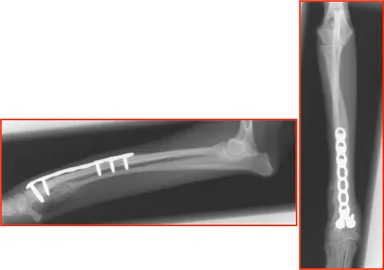

2. T字ロッキングプレートにて骨切り部の固定が良好に実施できることを確認

http://www.atpress.ne.jp/releases/54567/img_54567_6.jpg

<本手術>

・実骨切り時には模擬手術で使用した3Dプリンターモデルで骨切り線を確認しながら実施。

・模擬手術にて形状設定したプレートを使用しプレートに合わせ骨切り部の固定実施。(模型もインプラントも手術時には滅菌済)

・手術時間は切皮よりプレート固定まで40分(消毒・縫合時間を除く)

<術後8週 歩様>

・外観での右側前肢の外反も改善しており、歩様良好。

術前と術後の比較

http://www.atpress.ne.jp/releases/54567/img_54567_7.jpg

・骨切り部の良好な癒合所見。インプラントに異常は認められない。

術後8週間後 画像

http://www.atpress.ne.jp/releases/54567/img_54567_8.jpg